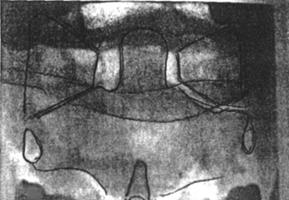

Рис. 55 Графическое изображение функционального блока атласа

1. Уменьшение величины боковой массы (признак ротации)

2. Латеральное смещение атласа относительно затылка и аксиса (признак латерального смещения)

3. Нарушение параллельности линий затылочной кости и аксиса (признак латерофлексии)